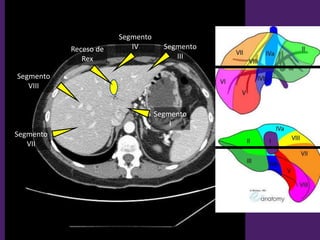

Bonus track:

Segmentación

del hígado

Vista Anterior. Vista Posterior.

Segmentación hepática

Vista superior Vista inferior

Segmento

II

III

IV a

VIII

VII

IV

I

Receso de

Rex

IV b

V

VI

L1-L2

L2